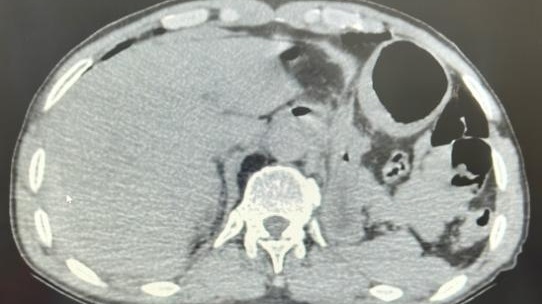

虽然是在医技科室开展援助工作,但作为医疗“侦察兵”的汤医生深知每一次精准的影像诊断都是对患者生命的尊重和守护。有一位患者因车祸伤来放射科进行胸腹部CT平扫检查,CT诊断为创伤性膈疝及肋骨骨折,但汤医生凭借其丰富的经验和敏锐的观察力,发现患者的肝脏外缘处有少许略高密度影及盆腔内血性积液,提示极大可能存在腹腔内脏损伤,该患者手术证实为局部肝破裂。汤医生的精准洞察不仅为患者及时解除病痛,更避免了潜在的严重并发症,充分展现了放射科医生在医疗团队中的重要角色,也为当地医生树立了榜样。